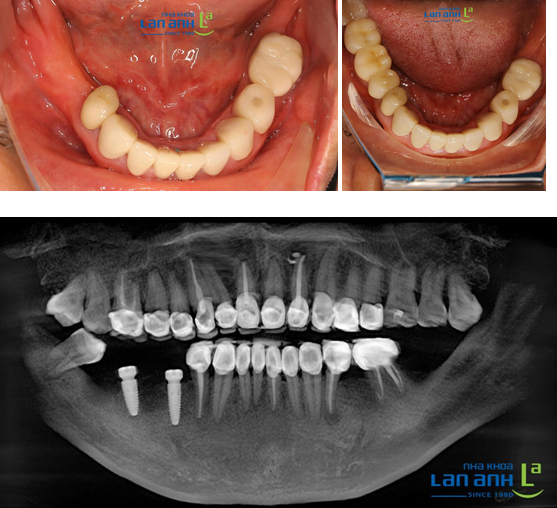

Một số trường hợp phục hình thẩm mỹ tại Nha Khoa Lan Anh